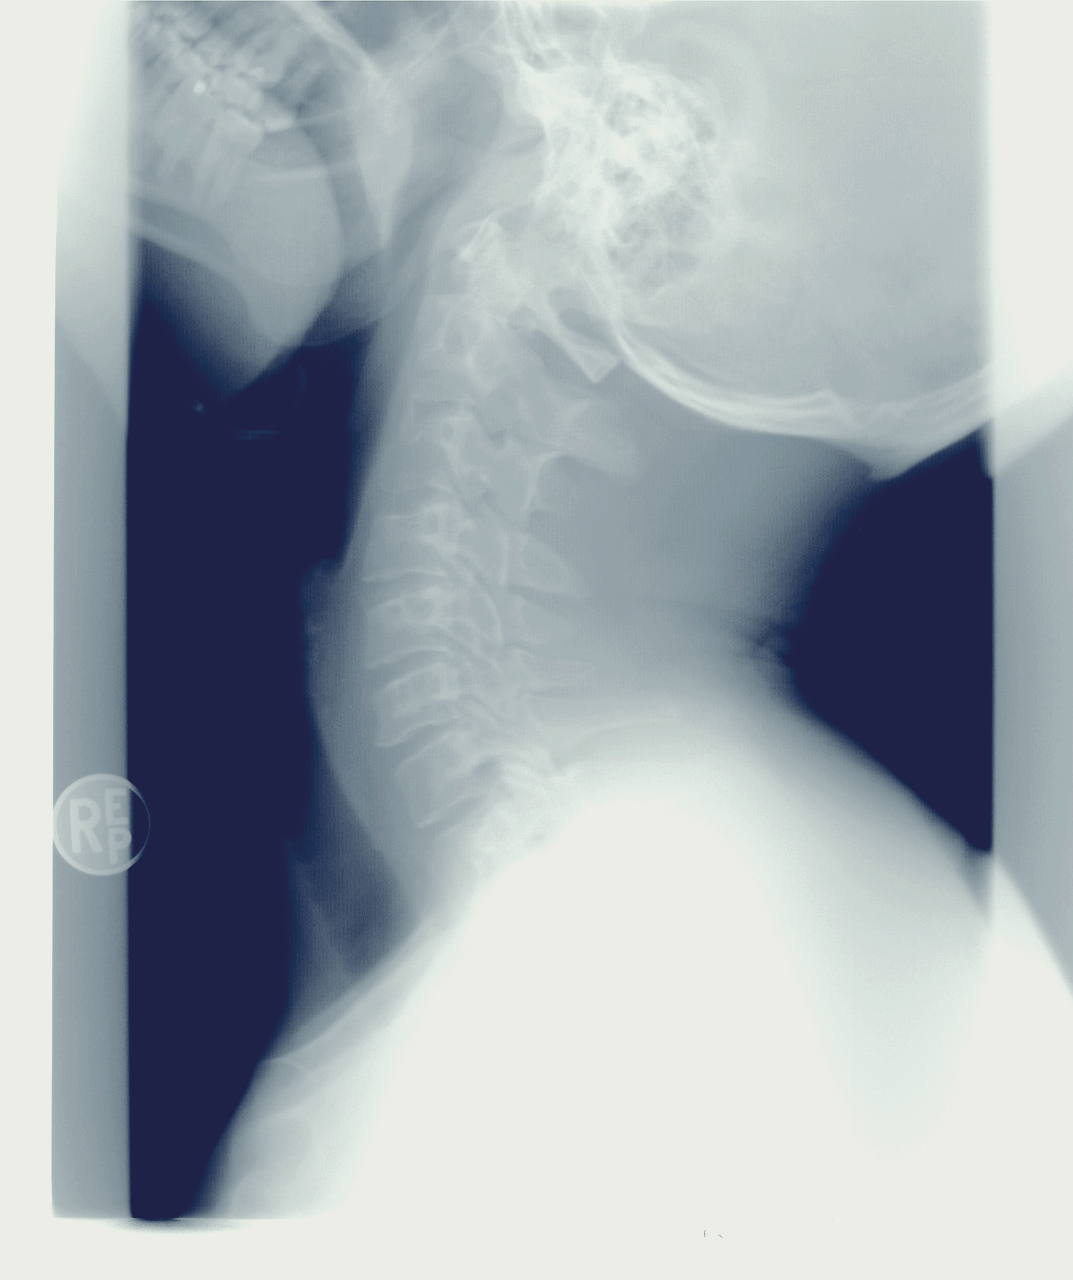

거북목은 말 그대로 목이 앞으로 굽어져 있는 상태를 말합니다.

거북목이 의심되는 경우 정확히 진단을 받고, 심한 정도를 확인하여 정확하게 거북목 교정을 받는 것이 중요하겠습니다.